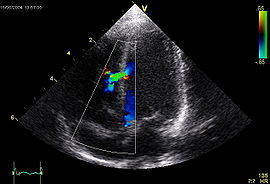

1. Ecocardiograma y ecografía de aparato reproductor y riñones